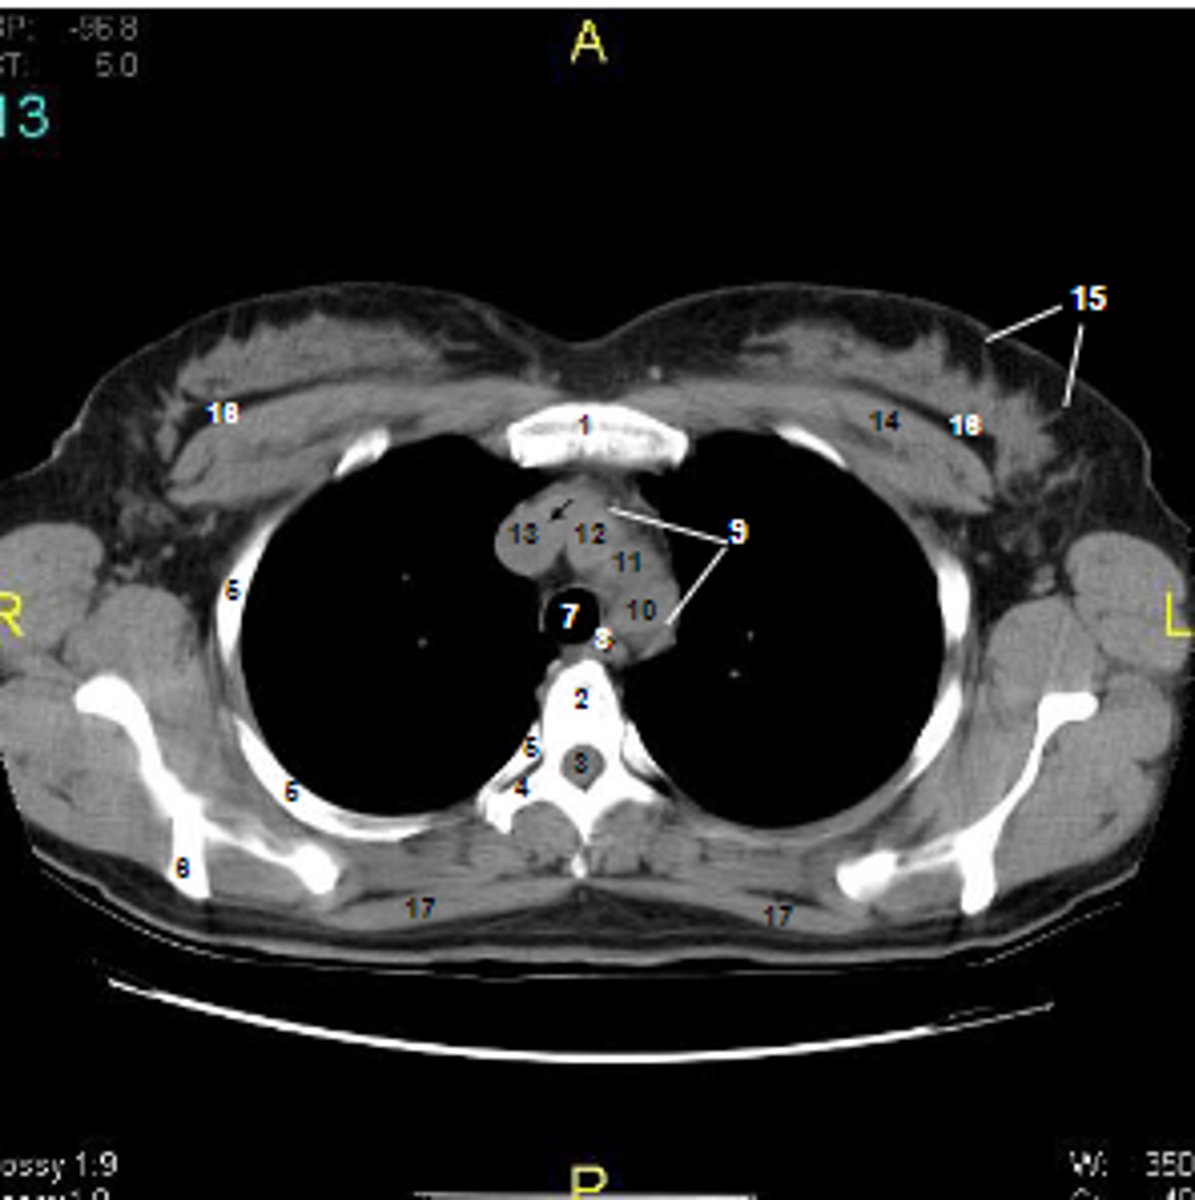

1

at what number is the sternum

2

at what number is the vertebral body

3

at what number is the vertebral canal/ spinal cord

4

at what number is the transverse process of vertebra

5

at what number is the rib

6

at what number is the spine of scapula

7

at what number is the trachea

8

at what number is the esophagus

9

at what number is the arch of aorta

10

at what number is the left subclavian artery

11

at what number is the common carotid artery

12

at what number is the brachiocephalic trunk

13

at what number is the superior vena cava

14

at what number is pectoralis major

15

at what number are Cooper's ligaments

16

at what number is the retromammary space

17

at what number is trapezius